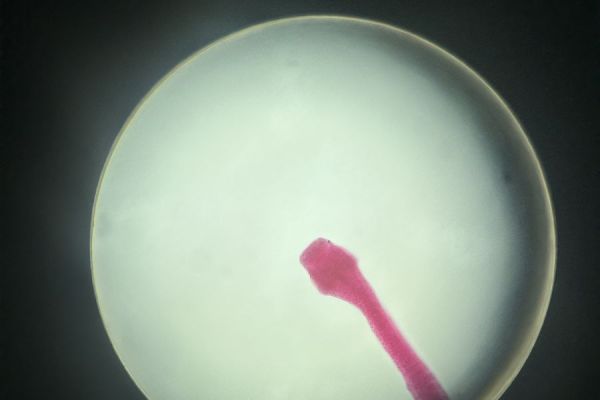

uczestniczyć w niezwykle ciekawych zajęciach w Zakładzie Biologii i Farmakognozji UMB. Podczas krótkiego, ale bardzo interesującego wykładu poznali cykle rozwojowe pasożytów, a następnie przenieśli teorię w praktykę, obserwując liczne preparaty mikroskopowe. Uczniowie oglądali m.in. lamblię, rzęsistka pochwowego, jaja tasiemca i glisty ludzkiej, wągry oraz główkę tasiemca uzbrojonego. Duże zainteresowanie wzbudziły również preparaty formalinowe tasiemca oraz wągra bąblowca.